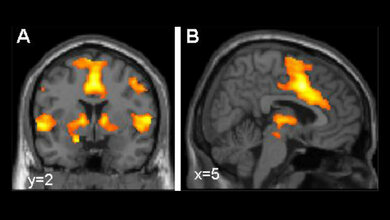

Dieses Gen kodiert in Gehirnzellen einen Mechanismus, der am Transport des wichtigen Botenstoffs Serotonin beteiligt ist. Diese Substanz dämpft unter anderem Angstgefühle und depressive Verstimmungen. „Das Ergebnis untermauert Hinweise vorangegangener Studien, dass Serotonin bei der sozialen Phobie eine wichtige Rolle spielt“, sagt Privatdozent Dr. Rupert Conrad von der Klinik und Poliklinik für Psychosomatische Medizin und Psychotherapie. Medikamente, die die Serotonin-Wiederaufnahme blockieren und die Konzentration des Botenstoffs in der Gewebeflüssigkeit des Gehirns erhöhen, werden bereits seit längerem zur Therapie von Angststörungen und Depressionen eingesetzt.